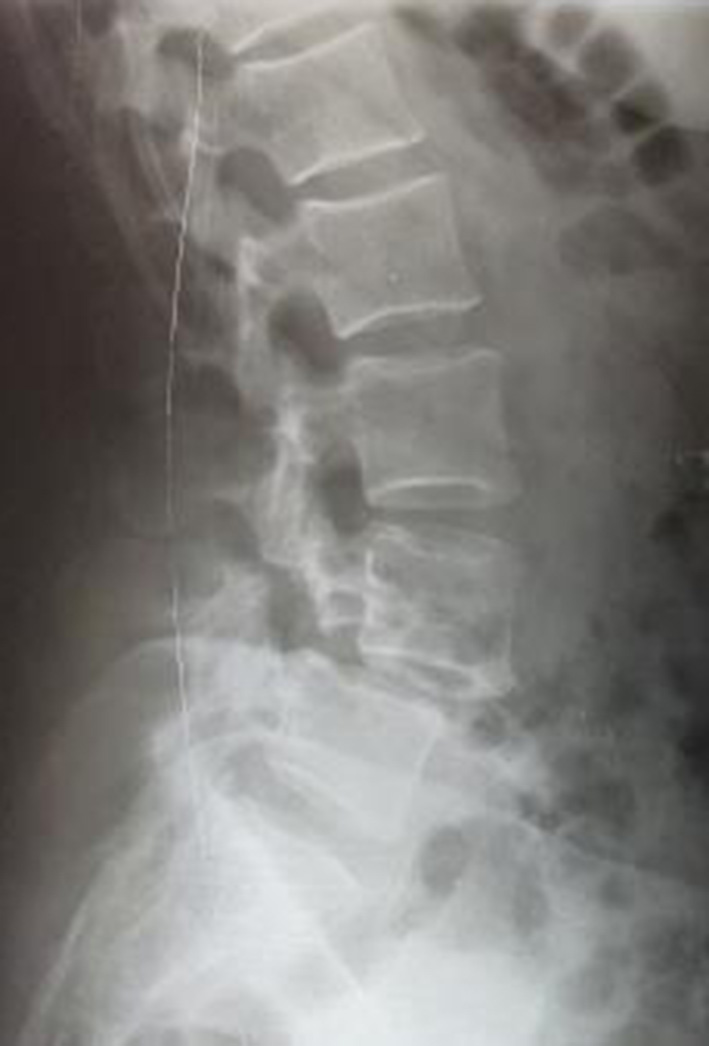

The clinical study involved 21 patients (15 women and 6 men), aged 32 to 68 years (median age – 56 (50; 65) years), divided into three groups: study group (n=4), where the author's technique of MIPIVS was applied (patent application No. a202302383 of 18.05.2023) (Fig. 3); comparison group (n=10), where the standard MIPIVS technique was used (Fig. 4); control group (n=7), where other interbody fusion techniques were employed (Fig. 5) .

Fig. 5. Radiographic control before and after surgery using alternative methods of lumbar interbody spinal fusion

Fig. 3. Radiographic control before and after surgery using the minimally invasive posterior interbody vertebral stabilization technique with titanium distraction cages

Fig. 4. Radiographic control before and after surgery using the traditional minimally invasive posterior interbody vertebral stabilization (MIPIVS) technique